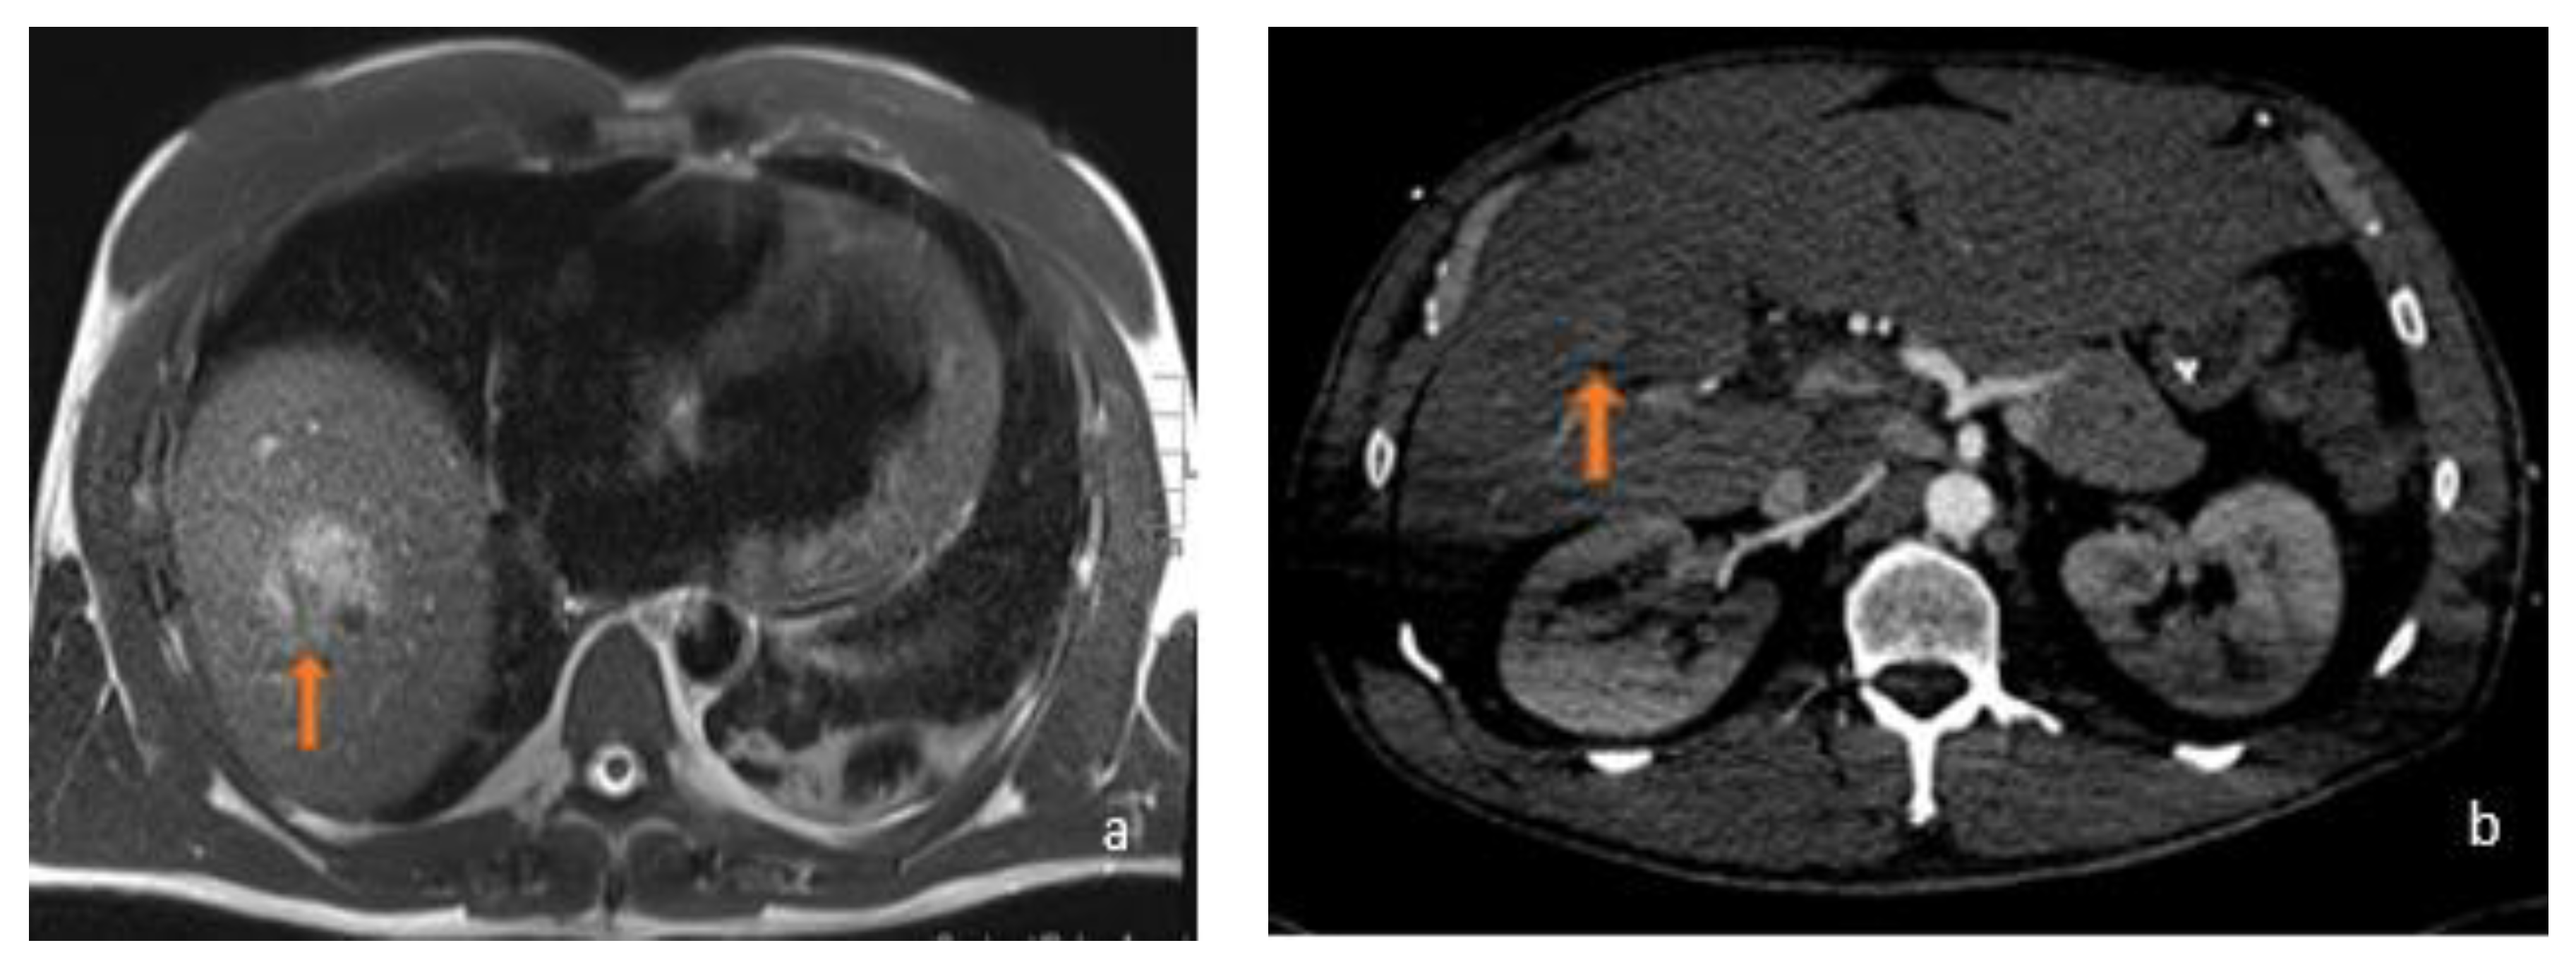

3.1. FLL Feature Characteristic

5.1. FLL Feature Characteristic